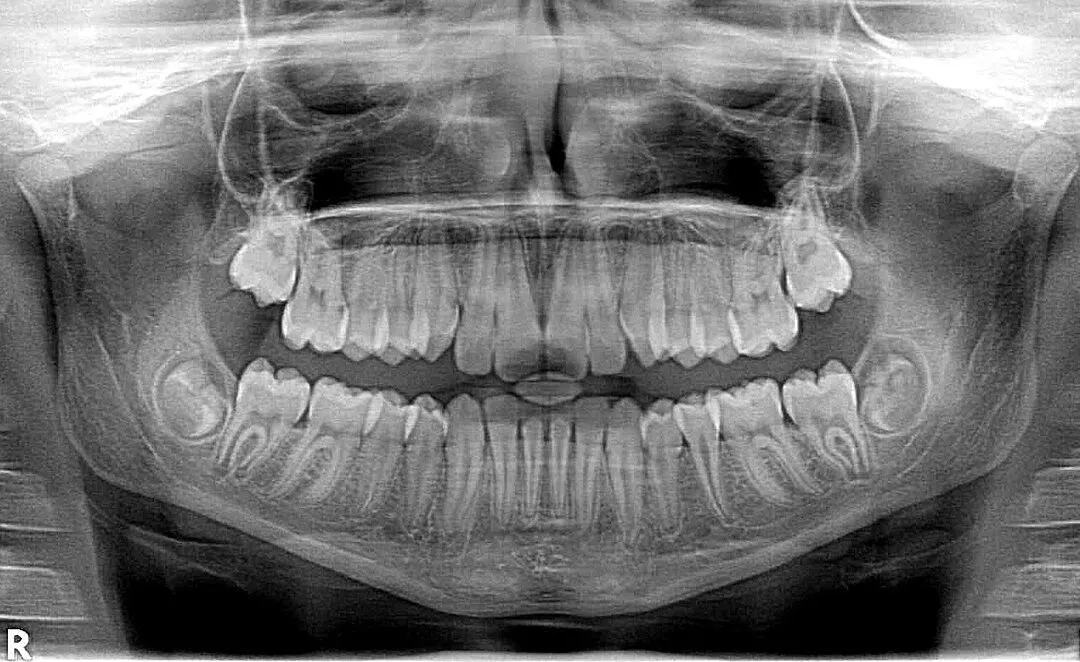

Le prix radio panoramique dentaire Maroc est une question fréquente pour les patients qui doivent réaliser un bilan complet avant un traitement dentaire ou orthodontique. Cet examen rapide et indolore offre une vue globale des dents, de l’os maxillaire et des articulations, facilitant un diagnostic précis.

Aussi appelée orthopantomogramme (OPG), elle consiste à réaliser une radiographie en arc qui englobe toutes les dents et les structures avoisinantes. C’est un outil indispensable avant un implant dentaire, une extraction de dents de sagesse ou un traitement orthodontique. Pour plus de détails locaux, voyez Radiologie dentaire à Tanger.

L’orthopantomogramme est prescrit avant la pose d’un implant, dans l’étude des dents de sagesse, pour détecter des kystes ou lésions, ou encore pour planifier un traitement orthodontique. Pour un suivi préventif, il peut être recommandé tous les 3 à 5 ans.